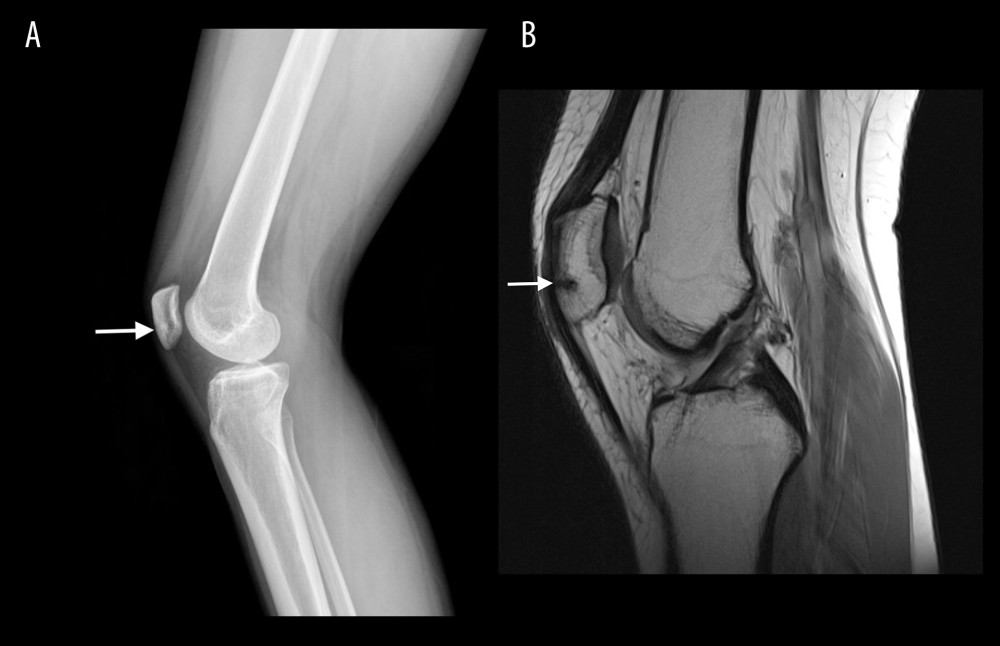

from amjcaserep.com

American Journal of Case Reports An 18YearOld Female Athlete Presenting with Knee Pain

American Journal of Case Reports An 18YearOld Female Athlete Presenting with Knee Pain Stress Fracture Knee Running What is a stress fracture and where are runners most likely to get them? Standard fractures are usually caused by a. A tibial shaft stress fracture is an overuse injury where normal or abnormal bone is subjected to repetitive stress, resulting in microfractures. Point tenderness is when a specific bone feels sore to the touch, and performing. What are the. Stress Fracture Knee Running.